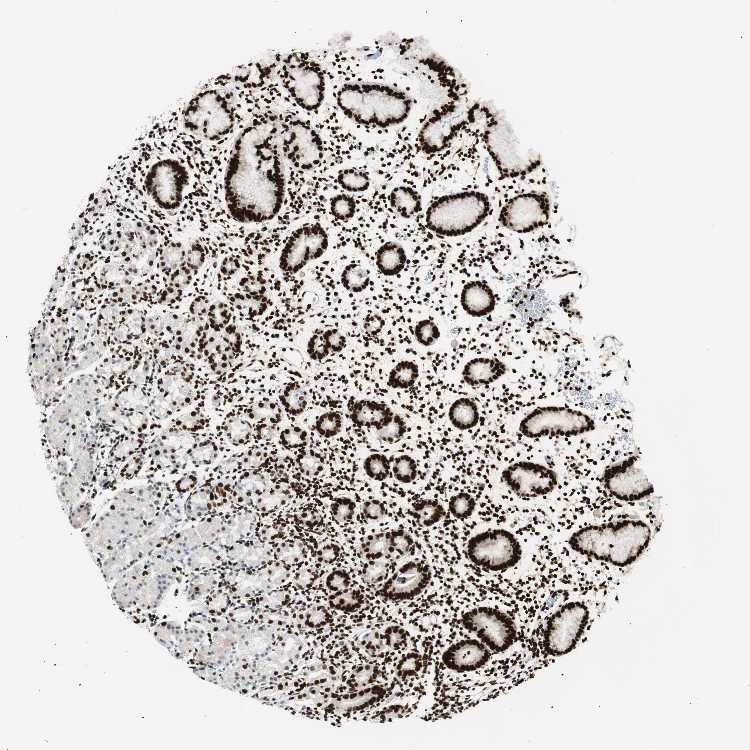

TISSUE PRIMARY DATA STOMACH Show tissue menu

STOMACH 1 - Antibody stainingi

Antibody staining in the annotated cell types in the current human tissue is reported as not detected, low, medium, or high, based on conventional immunohistochemistry profiling in selected tissues. This score is based on the combination of the staining intensity and fraction of stained cells.

Each image is clickable and will lead to virtual microscopy that enables deeper exploration of all samples and also displays staining intensity scores, fraction scores and subcellular localization as well as patient and tissue information for each sample.

Antibody HPA051771Antibody HPA062953Antibody CAB004230

Glandular cells HighHighHigh